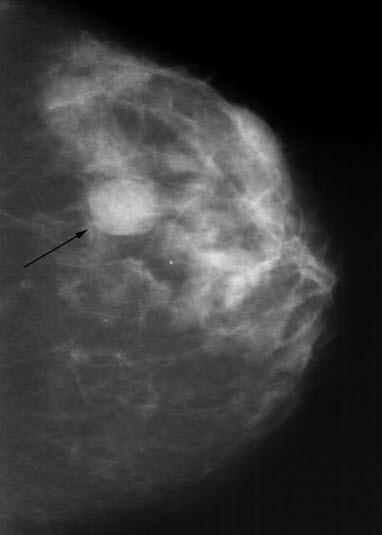

Mammografi, cyste

Tett, homogen, velavgrenset fortetning sentralt i brystet. Utseendet gir mistanke om cyste, dette må bekreftes med ultralyd.